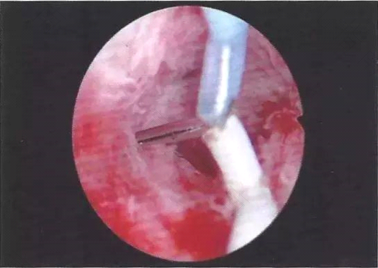

宫颈红肿不是一种疾病名称,它只能作为妇科疾病的一种表现形式,如阴道炎、宫颈炎、宫颈糜烂等患者可能会有宫颈红肿。宫颈发红的症状包括异常阴道出血、疼痛、异常阴道分泌物和阴道疼痛。